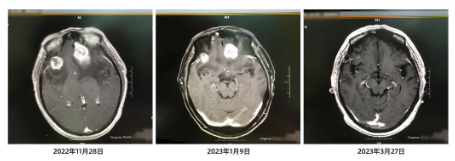

然而,疾病的魔爪卻步步相逼。去年11月27日,鄧先生在家中突然出現(xiàn)白天嗜睡,夜間興奮,小便失禁,答非所問(wèn),陣發(fā)性精神錯(cuò)亂。家人立即帶他來(lái)瑞康醫(yī)院就診,頭顱MR平掃,診斷為:肺惡性腫瘤腦轉(zhuǎn)移。

“患者基因檢測(cè)未發(fā)現(xiàn)相關(guān)突變,靶向藥物不可用,現(xiàn)在又出現(xiàn)腦轉(zhuǎn)移,且雙側(cè)額葉病灶較大的約2.68cm*2.89cm?!泵鎸?duì)盤(pán)桓在鄧先生治療路上的難題,朱小霞根據(jù)多年臨床經(jīng)驗(yàn)及對(duì)患者愈后的估計(jì),綜合腫瘤用藥經(jīng)驗(yàn),決定采用“免疫+化療+抗血管生成藥”聯(lián)合用藥治療。

四期治療后,3月27日,鄧先生頭顱MR平掃,發(fā)現(xiàn)其右側(cè)額葉見(jiàn)一個(gè)環(huán)形顯著強(qiáng)化影,長(zhǎng)徑約0.65cm。這與1月9日在進(jìn)行“免疫+化療+抗血管生成藥”聯(lián)合用藥治療之前相比,病灶明顯縮小,達(dá)到部分緩解。

朱主任告訴記者,臨床上,肺癌腦轉(zhuǎn)移的患者實(shí)現(xiàn)部分緩解是比較少見(jiàn)的。同時(shí),朱主任還特別強(qiáng)調(diào),抗癌是一場(chǎng)持久戰(zhàn),不僅需要合理有效的治療手段,也需要患者積極樂(lè)觀的心態(tài)。